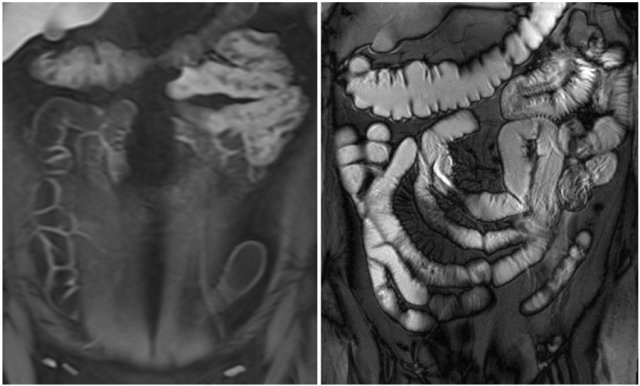

Here we see a coronal T2W-image and a coronal T1W-image with fatsat.

Notice that the small bowel is well distended.

Luminal distension should be ≥ 2 cm.

Bowel wall thickness > 3 mm is considered abnormal.

Collapsed small bowel loops can be easily misinterpreted as wall thickening or abnormal enhancement.

On the coronal T1W-image the jejunal loops are collapsed.

As a result it looks as if there is bowel wall thickening and prominant enhancement.

On the T2W-image during the same examination there is normal distention.